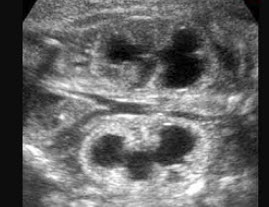

172、单项选择题

如图,36周胎儿,最可能的诊断是()